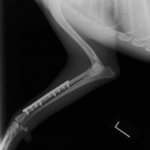

症例3:キルシュナーワイヤーのピンニングによる整復

ペルシャ猫 11ヶ月齢 雄

他院にて左大腿骨遠位の成長板骨折(salter-harrisⅠ型)が認められており、治療相談を目的として来院。当院にて、キルシュナーワイヤーを用いたピンニングにより骨折部位の整復を行いました。術後の経過は良好で、現在も経過観察中です。

術前レントゲン

術後レントゲン